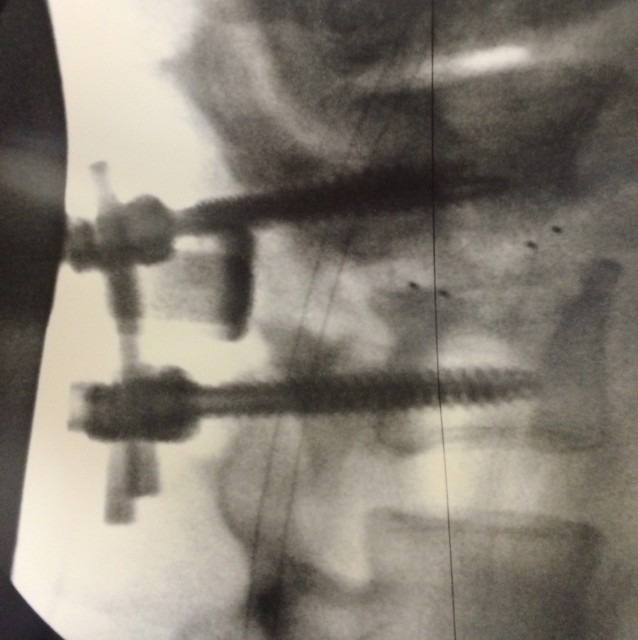

“These are 2 screws my Dr inserted into my lower back to ease the pain and numbness I was experiencing. They are in my lower back L3-4. Wan so much looking the day can get back to the gym and lift some lightweight baby. As I always say, once I get back it’s gonna be on like a fire zone.